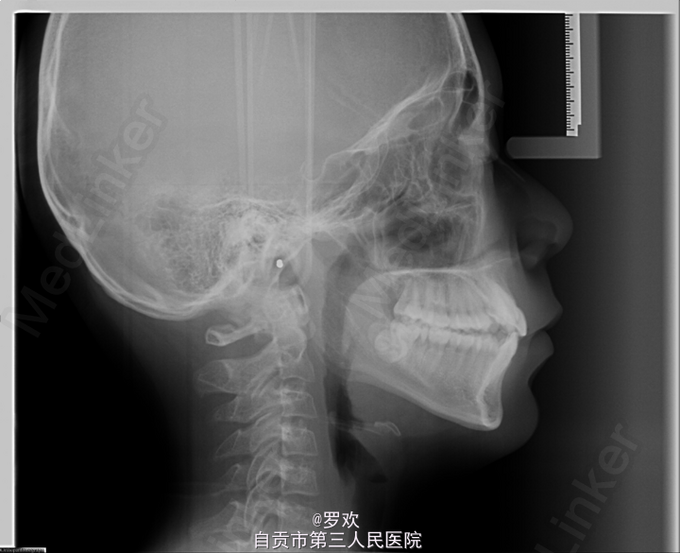

主诉:牙齿排列不整齐 女 11岁,生长发育高峰期 ,牙列拥挤

磨牙远中关系; 上颌重度拥挤; 上颌双侧3低位唇向; 右侧后牙反合。

诊断:骨性Ⅰ类、安氏Ⅱ类亚类;稍高角、平均生长型;上颌双侧3低位唇向;上颌重度拥挤;右侧后牙反合。 处理:拔牙矫治(直丝弓矫治技术) 1. 拔除4|4 ,后牙重度支抗(TPA+口外弓),排齐排平上下牙列,拔牙间隙用于解除上颌牙列拥挤及纠正磨牙关系至完全远中关系。协调上下牙弓形态并配合交互牵引纠正右侧后牙反HE 。 2. 排齐排平牙列后,如觉面形较凸可再诊下颌拔牙。 3. 治疗结束后,透明保持器保持。